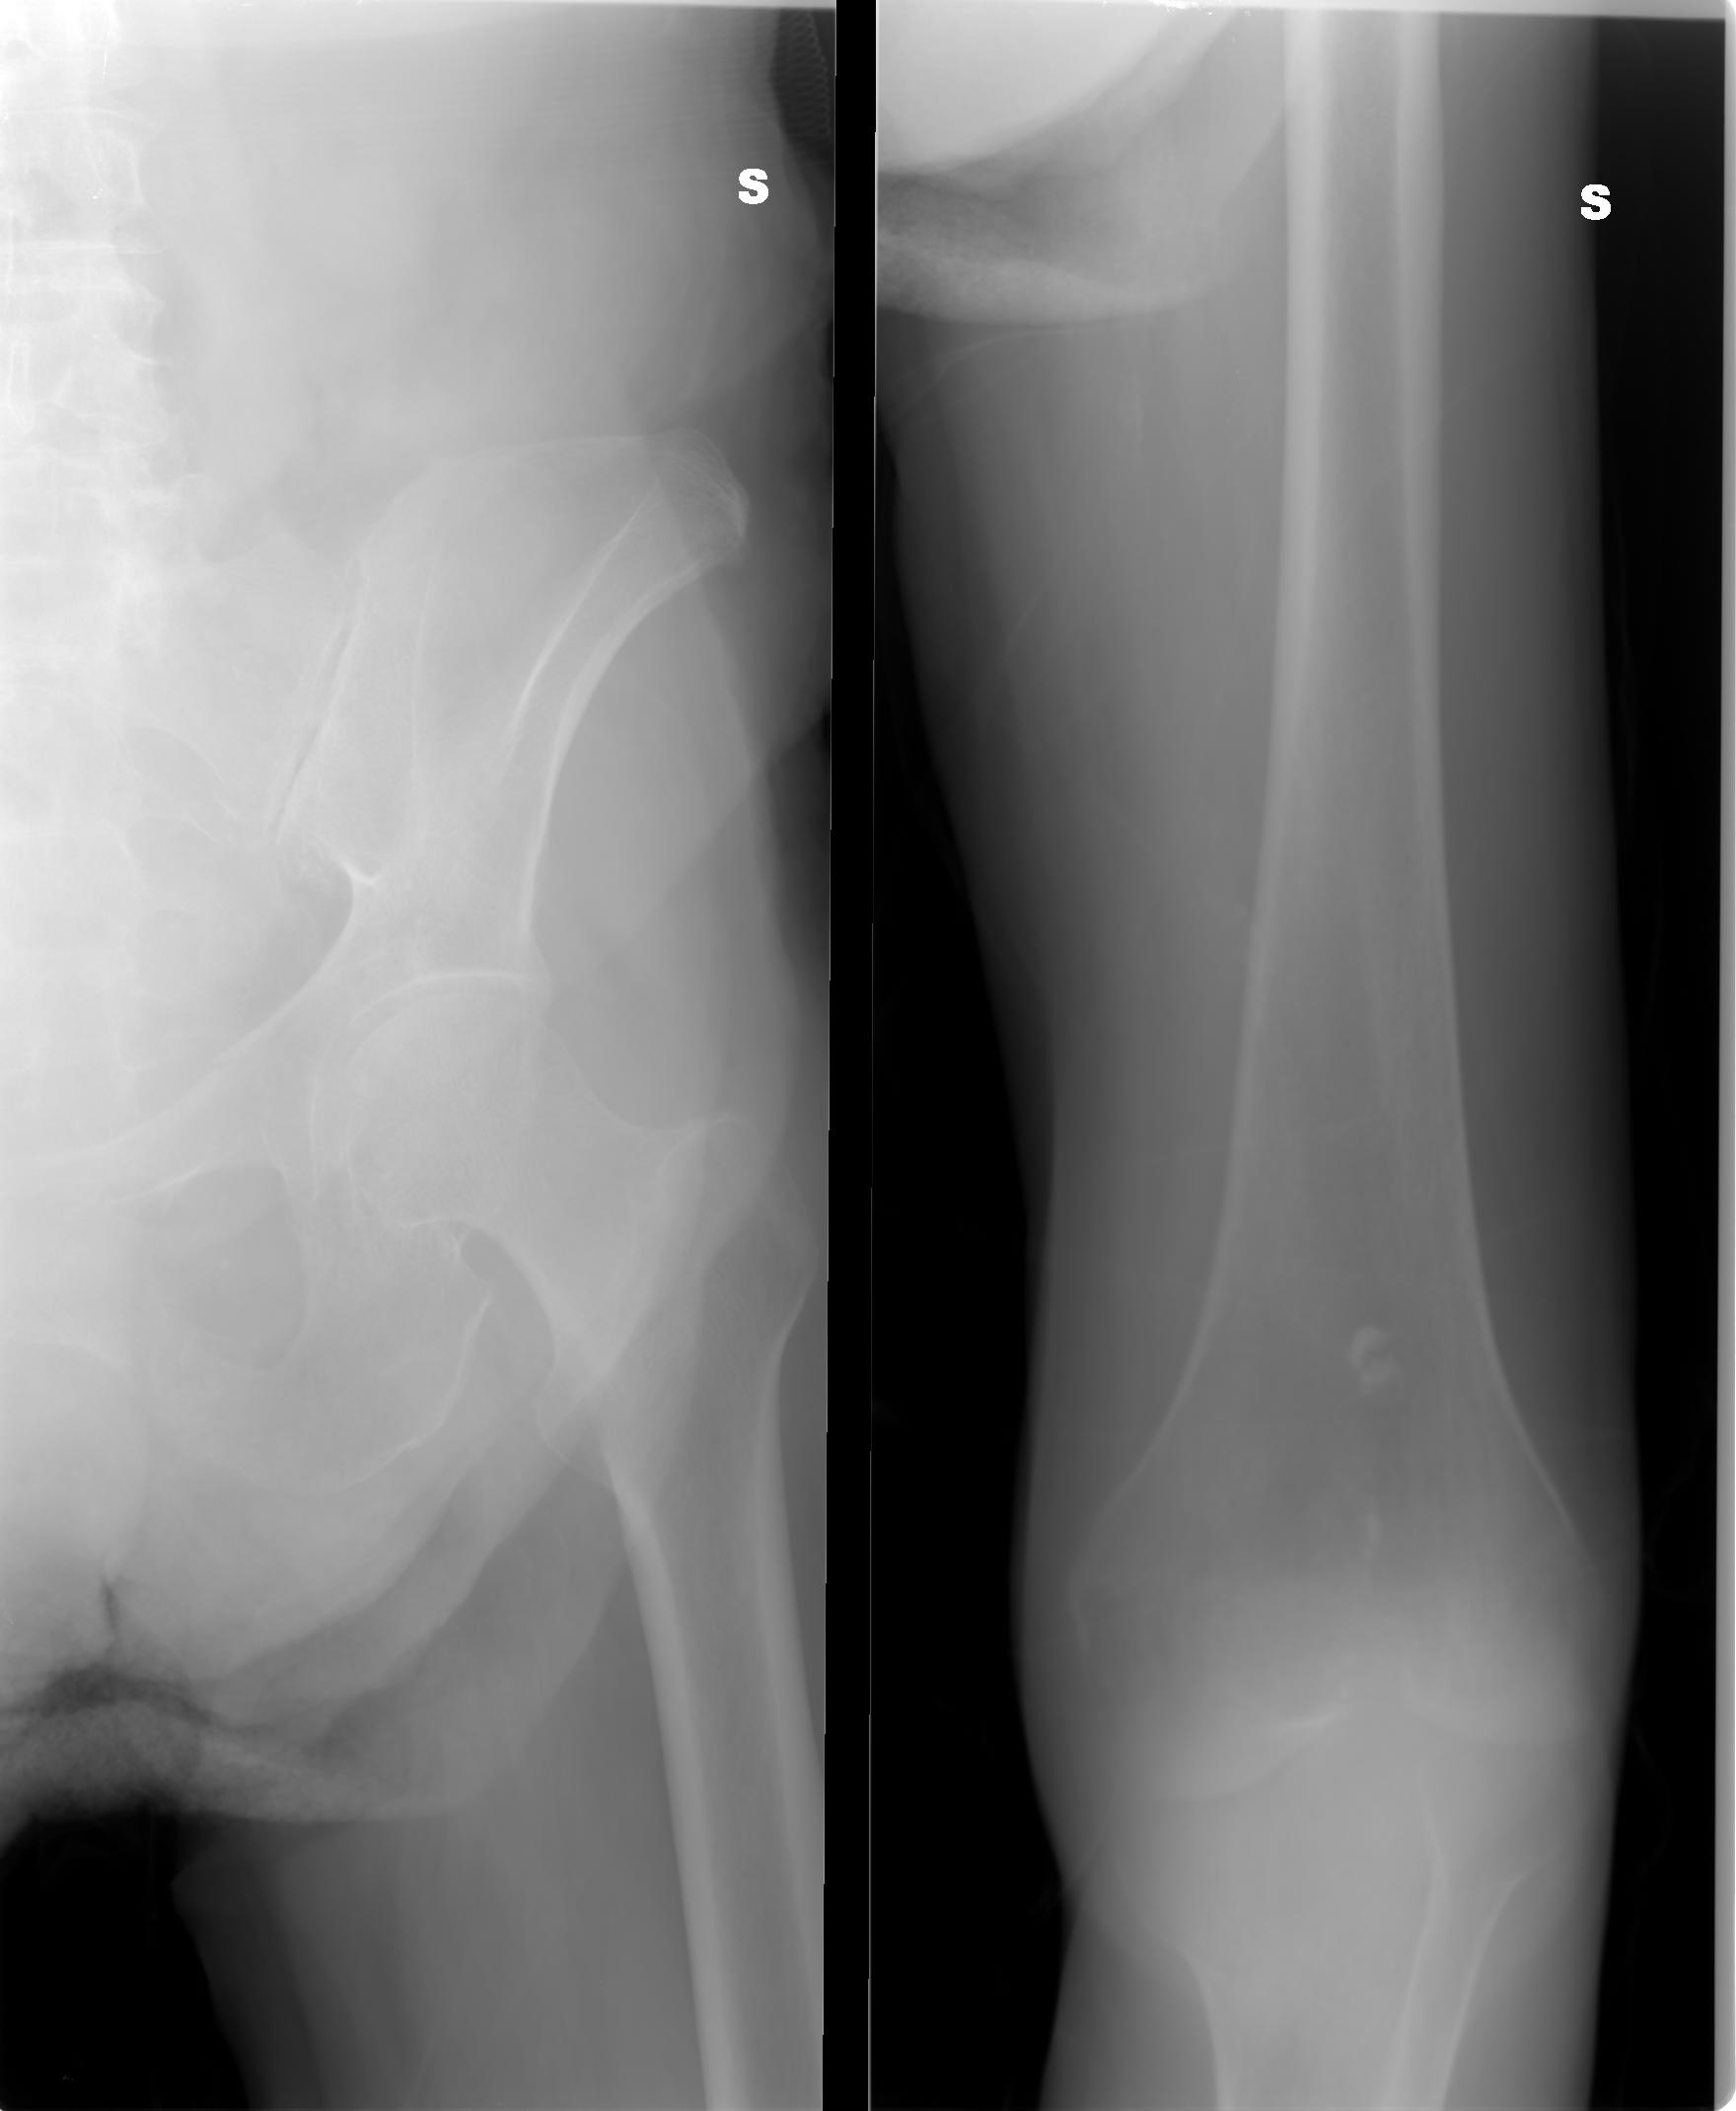

SALVE, ho ritirato un referto lastra per mia madre 80 anni e dice le seguenti parole: per quanto apprezzabile nel radiogramma a disposizione si osserva frattura composta della branca ile pubica sinistra .Sospetta frattura (o esiti fratturativi?) a carico dell branca ischio pubica omolaterale.

allego le lastre potete consigliarmi?